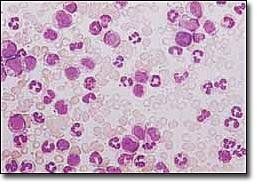

1.周圍血象 主要為白細胞增多,80%在100×109/L以上。血色素在80g/L左右。血小板增多。分類可見粒系增多,包括嗜酸、嗜鹼粒細胞增多。原始粒細胞增多不明顯,以中、晚幼和成熟粒細胞為主。

3.骨髓檢查 增生活躍,以粒系增生為主,原始粒細胞<10%,多為中晚幼粒細胞及桿狀核細胞粒∶紅為10~50∶1。部分患者可見骨髓纖維化。骨髓巨核細胞明顯增多,以成熟巨核細胞為主。骨髓培養集落與叢落皆增多